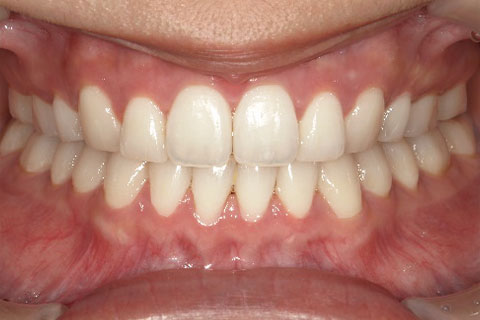

主訴:上下の歯並びのガタガタが気になる

診断名:上下顎叢生

症状:上下顎叢生

患者プロフィール:北九州市・小倉北区30代女性

治療方針:非抜歯治療

治療装置:マウスピース型矯正治療(インビザライン)

抜歯:無し

治療期間:一年半

通院回数:30回

リテーナー:上顎プレートタイプリテーナー 下顎フィクスタイプリテーナー

治療費用:検査診断料(20,000)+装置料金(500,000)+管理調整料(150,000) +装置撤去時診断料(10,000) +保定装置料金(20,000)=700,000(消費税込)

リスク副作用:痛み・治療後の後戻り・歯根吸収・歯髄壊死

詳しい症例説明:この患者さんはガタガタが気になり来院されました。マウスピースタイプの矯正装置で比較的短期間で治療を終えることができました。インビザライン(マウスピース矯正治療)で矯正治療を行うことで取り外して食事ができ、痛みもそれほど感じなかったとのことです。